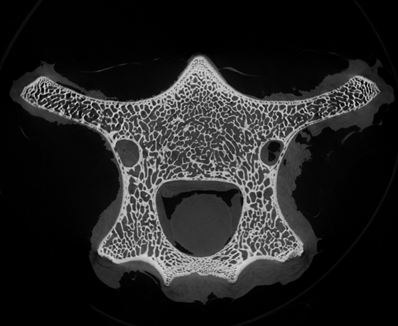

小編很好奇在micro CT掃描中,這些笑臉會(huì)是什么樣子?我們選擇了一段羊的脊椎骨放入CT設(shè)備中進(jìn)行掃描,在得到的幾百?gòu)埱衅瑘D中,挑選出一張“萌萌的大笑臉”。

Step1. 獲得CT三維體數(shù)據(jù)

骨骼CT切片圖